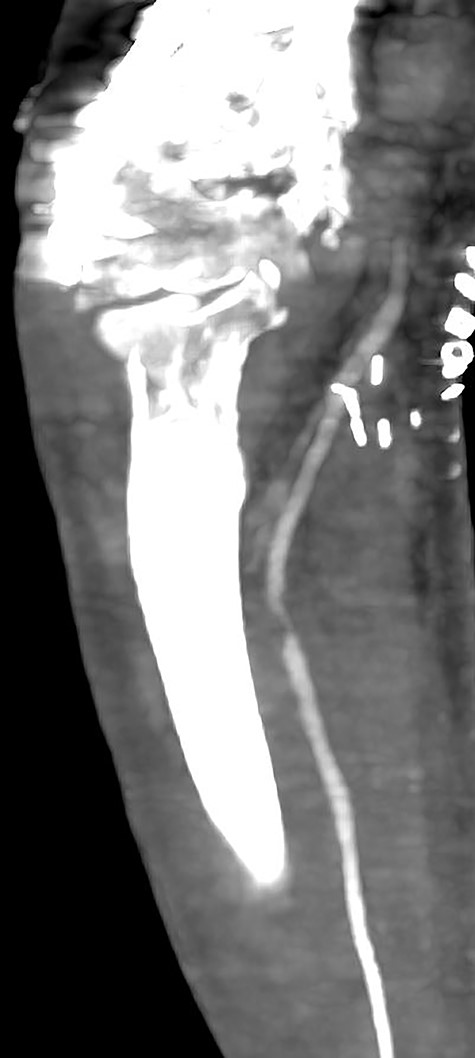

Seven days later, while his general condition was deteriorating, he developed acute ischemia in his right thumb and index finger (Fig. 2). In the ipsilateral forearm, a radial artery catheter had been inserted for monitoring. An urgent radial artery embolectomy was performed and restored the arterial supply to the right hand. The antithrombotic agent was changed to fondaparinux (7.5 mg/once daily). However, within the next few days, it was clinically evident that the revascularization effort was unsuccessful as the thumb and index finger developed dry gangrene. On examination, there was no palpable radial pulse, the ulnar artery pulse was palpable at the level of the wrist and the capillary refill time was normal at the middle, ring and little fingers. A CT angiography (Figs 3 and 4) was performed, demonstrating complete thrombosis of the radial artery beginning at the level of the elbow as well as a 70% occlusion of the ulnar artery ~15 cm proximal to the wrist. Thrombosis of the right axillary vein was also seen (Fig. 5). Orthopedic review was requested for consideration for finger amputation with a recommendation for arm amputation at the level of the elbow. Unfortunately, the patient died 72 h later from respiratory failure following a 24-day admission in ICU.

Multiplanar reformation image shows severe near occlusion 6-mm stenosis of the ulnar artery.